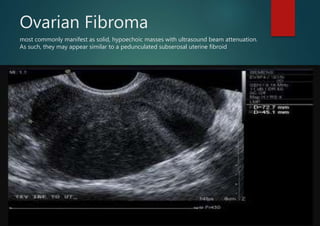

Ovarian Fibroma

most commonly manifest as solid, hypoechoic masses with ultrasound beam attenuation.

As such, they may appear similar to a pedunculated subserosal uterine fibroid